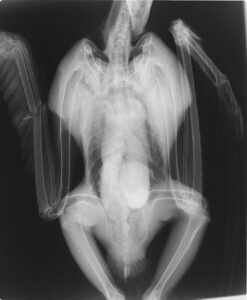

2014年1月23日苫前町の風力発電施設の風車の下でうずくまっている所を発見されたオジロワシがWLCに搬送されてきました。釧路まで約400㎞の雪道を道内各所にある環境省事務所の連携によるリレー方式で搬送し、夜10時頃WLCに到着しました。右側の橈骨と尺骨が骨折し、また低体温と脱水で非常に衰弱していましたが、当日中に運んでくれたお陰ですぐに処置を開始することができ、一命を取り留めることができました。

橈尺骨の骨折

これまで風車との衝突事故に遭遇したワシの場合、骨は粉砕していることが多く、今回のオジロワシの骨折状況から推察すると、風車による気流の乱れに巻き込まれたか、ブレードにかするような形で接触し、高所から落下して骨折が生じたことが推察されました。骨折部位はピンニング処置を施しましたが、大切なのはこの後のケアです。骨折の状況から、橈骨と尺骨が一緒に癒合してしまう可能性があり、そうなると翼の開閉に支障が生じて上手く飛ぶことができなくなります。こまめな診察とリハビリが必要です。